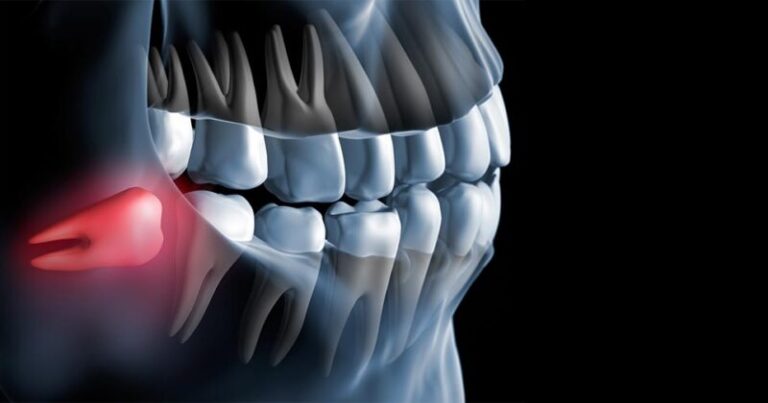

Siso irrompido (visível na boca)

Extração simples, normalmente realizada em consultório com anestesia local e tempo reduzido.

O siso pode nascer em posições diferentes, muitas vezes sem aparecer totalmente — por isso, cada caso precisa ser avaliado e planejado para que a extração seja feita com segurança.

Extração simples, normalmente realizada em consultório com anestesia local e tempo reduzido.

Quando o dente nasceu parcialmente. Requer pequena cirurgia com planejamento por tomografia.

Dente preso no osso ou na gengiva. Cirurgia odontológica com técnica avançada e segurança máxima.

Casos delicados que exigem tomografia computadorizada para extração precisa, evitando complicações.